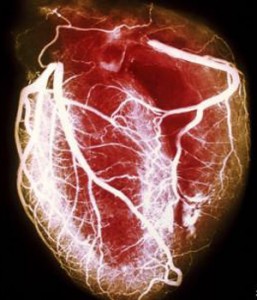

O estudo, feito pelo Medical Research Council da Grã-Bretanha, sugere que variantes do gene IRS1 reduzem a gordura sob a pele, mas não têm efeito sobre a gordura presente nas vísceras, em torno de órgãos como o coração e o fígado – muito mais perigosa.

“Esses resultados reforçam a ideia de que, para riscos ao coração, é particularmente importante não apenas quão obeso você é, mas sim onde você deposita a gordura.”

“A gordura armazenada internamente é pior para você do que a armazenada sob a pele.”

“Entretanto, isto não elimina o fato de que ser obeso é ruim para a saúde do seu coração, então devemos continuar tentando ficar magros e em boa forma física.”